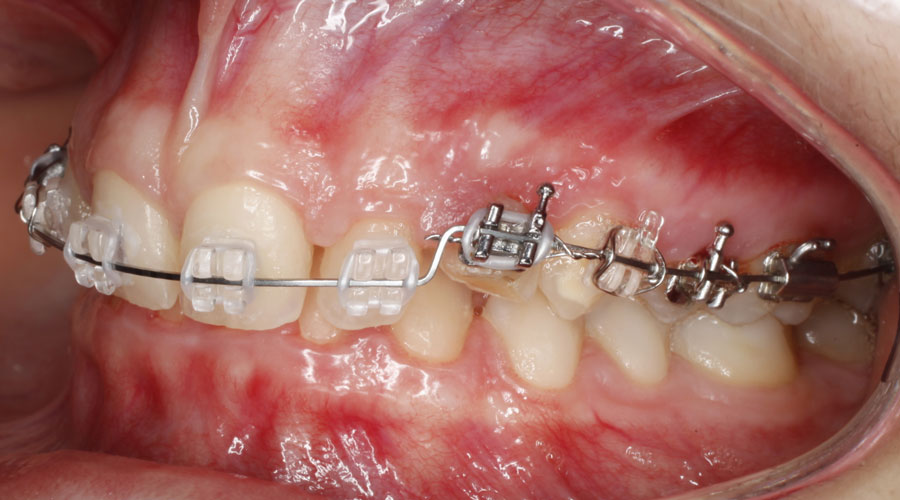

Caso clínico 2. La paciente presentaba Clase II dentaria división 2ª, con gran sobremordida, además de erupción ectópica de los caninos superiores. Se realizó ortodoncia multibracket transparentes con cirugía de fenestración de ambos caninos. Debido a la posición de éstos por palatino, colocamos dos microtornillos para ayudarnos en su tracción y poder separar la corona de las raíces de los incisivos. Posteriormente, traccionamos desde la cara vestibular con ayuda de un resorte para colocarlo en su lugar en la arcada.